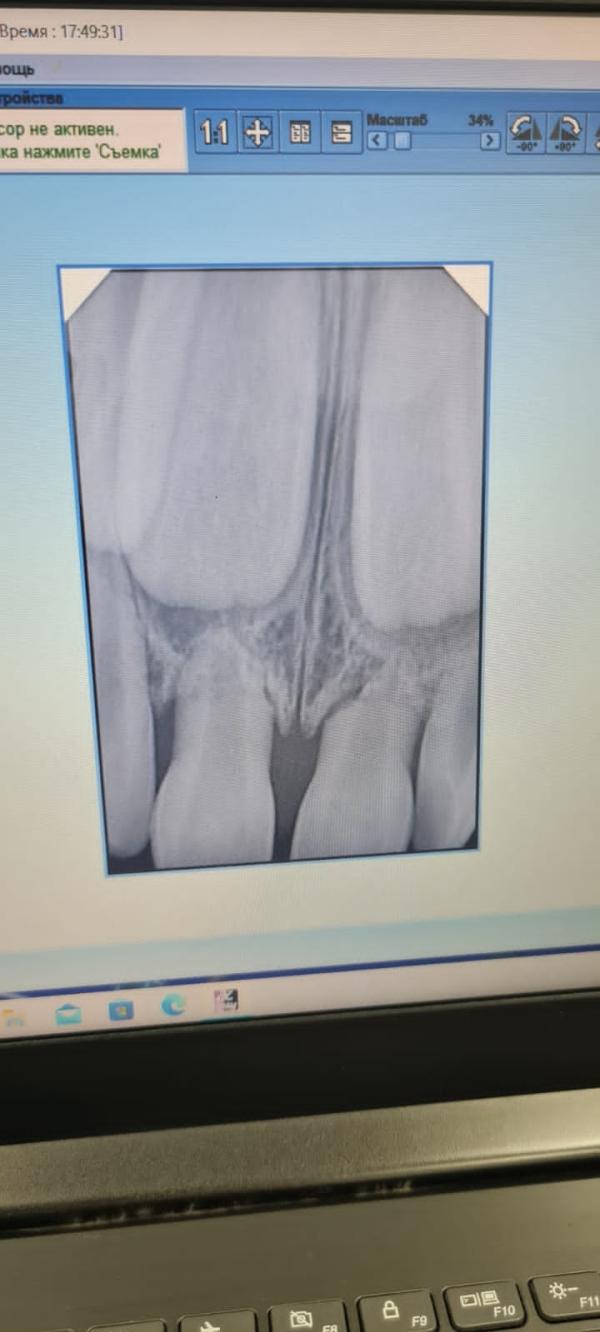

Запись в Витар в этот же вечер. Прием. Вердикт: шатаются три передних зуба + два новых кариеса (заодно увидели). Снимок. А там, как оказалось, на одном из центров уже истончен корень, т.е. зуб готовится ...